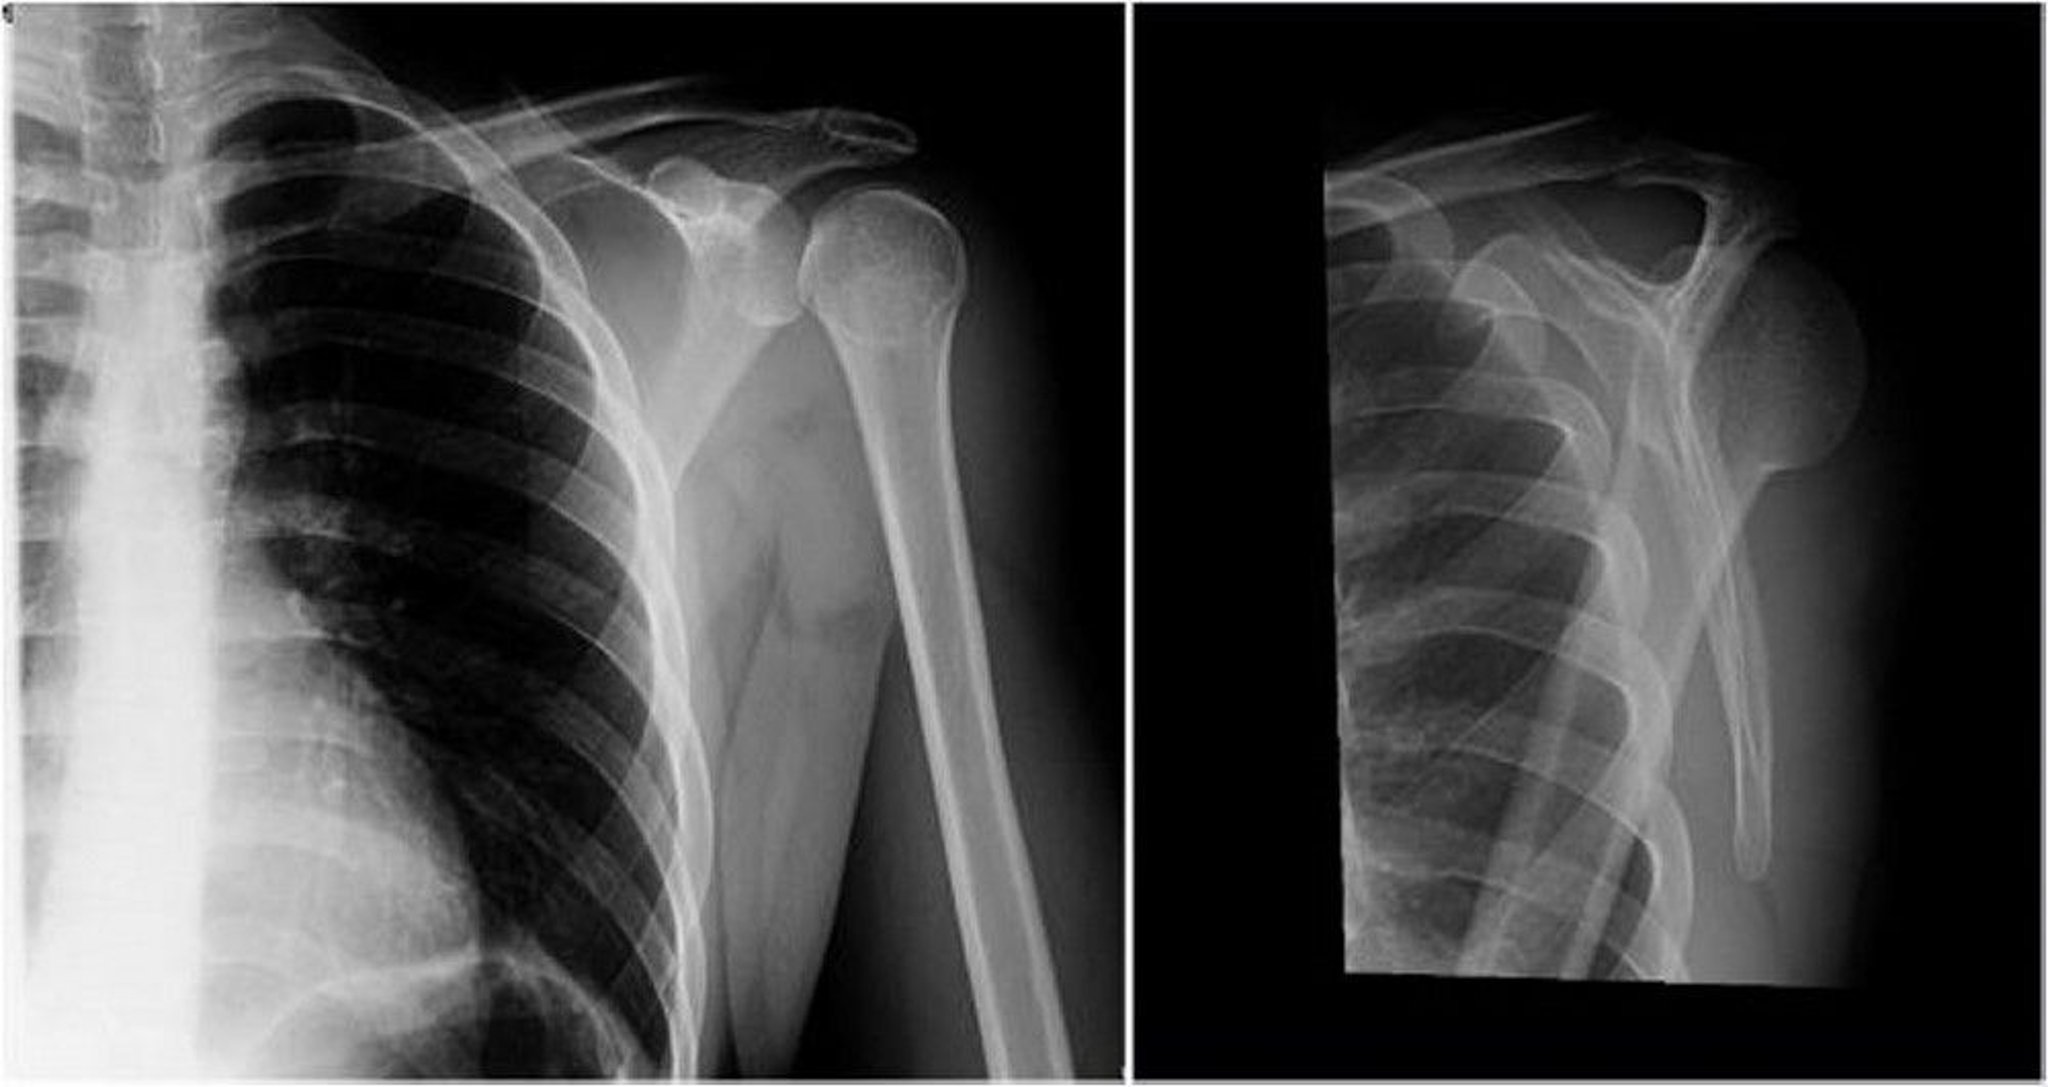

Posterior Shoulder Dislocation: Anteroposterior and Y Views

In the left image (anteroposterior view), the humeral head is internally rotated, resulting in the light bulb or ice cream cone sign (projections of the greater and lesser humeral tuberosities are not seen), which suggests a posterior dislocation. In the right image (Y view), the humeral head is posterior to the glenoid fossa, which demonstrates a posterior dislocation.